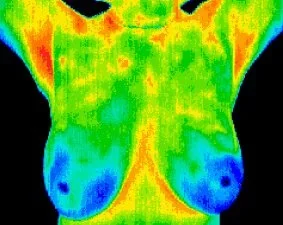

Breast Thermography Scan

This imaging series is for the breast region only. It includes:

- Full frontal image

- Lymph node regions in the front and both sides of the body

- Individual breast images

The conditions identified focus on abnormalities within the breast tissue caused by conditions such as:

- Breast inflammation

- Fibrocystic breast tissue

- Inflammatory Breast Disease

- Breast Mastitis

- Cystic breast tissue

- Lymphatic congestion

- Monitoring breast disease activity